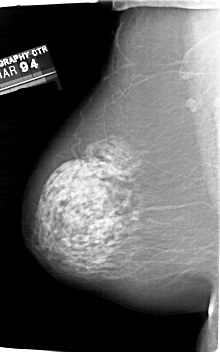

A_1829_1.RIGHT_CC

RIGHT_CC LINES 6601 PIXELS_PER_LINE 4036 BITS_PER_PIXEL 12 RESOLUTION 43.5 OVERLAY

FILE: A_1829_1.RIGHT_CC.OVERLAY

TOTAL_ABNORMALITIES 1

ABNORMALITY 1

LESION_TYPE CALCIFICATION TYPE PLEOMORPHIC DISTRIBUTION CLUSTERED

ASSESSMENT 4

SUBTLETY 3

PATHOLOGY BENIGN

TOTAL_OUTLINES 1

BOUNDARY